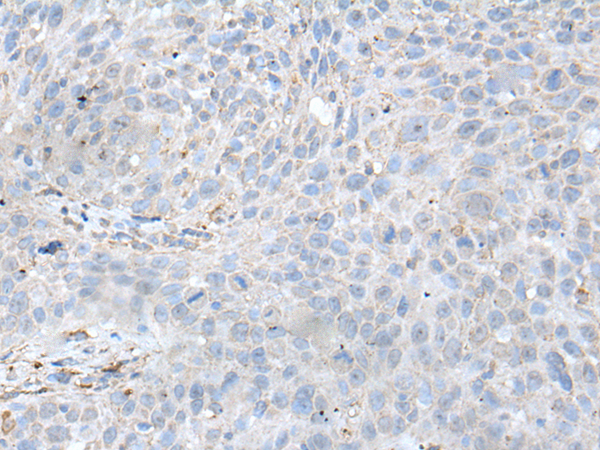

分类: 科研抗体货号: P09349别名: G5; BAT4; D6S54E; ANKRD59; GPATCH10应用: IHC反应种属: Human, Mouse